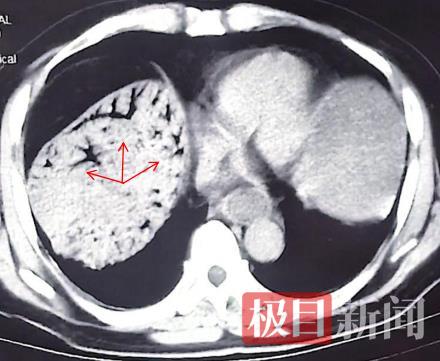

箭头所指为门静脉积气征CT“树枝状”表现

随行的朋友赶紧将他送往附近医院就诊。经急诊CT检查,发现他肝门静脉主干及分支存在大量气体影,呈“树枝状”,初步诊断为“门静脉积气”。这是一种危急重症,往往是由于肠道黏膜屏障被破坏,肠腔内气体经破损的血管进入门静脉系统所致。临床上较为少见,但一旦出现,通常提示有严重的潜在疾病,如肠缺血、肠坏死、肠梗阻、炎症性肠病或产气杆菌感染等,死亡率高达75%。医生当即建议他们迅速转至武汉大学人民医院。